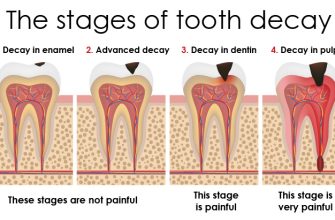

1. Arthritis: Arthritis is a common cause of joint stiffness and pain. Osteoarthritis, the most prevalent form, occurs when the protective cartilage that cushions the ends of bones wears down over time. Rheumatoid arthritis, an autoimmune disease, causes joint inflammation and can lead to chronic joint pain.